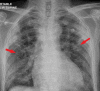

BACKGROUND Coronavirus disease 2019 (COVID-19) caused by severe acute respiratory syndrome coronavirus 2 (SARS-CoV-2) primarily affects the lungs but can involve any organ. The medical community is struggling to cope with the critical illness associated with the disease. On top of that, patients who have recovered from COVID-19 have presented with complications such as thrombotic episodes in various organs both during and after being infected with SARS-CoV-2. A COVID-19-associated prothrombotic state has been mentioned in multiple recent research articles. The role of anticoagulants is debatable, because even after receiving them prophylactically, many patients have experienced thrombotic episodes. The situation, therefore, represents a challenge to the medical community. CASE REPORT We report on a COVID-19-associated prothrombotic state in a 65-year-old man with no history of comorbid illness. Initially, he presented with right-sided weakness and was found to have had an acute ischemic stroke. Urgent imaging after the stroke revealed changes on electrocardiography that were remarkable for left bundle branch block. The patient's elevated cardiac enzyme levels correlated with a silent acute myocardial infarction (MI). His echocardiogram revealed a left ventricular (LV) thrombus. He was managed with a multidisciplinary approach involving Neurology, Cardiology, and Medicine. CONCLUSIONS COVID-19-associated prothrombotic episodes involving arterial and venous systems have been reported in the literature. But concomitant stroke, acute MI, and LV thrombus rarely have been documented. The role of prophylactic or therapeutic anticoagulation is still unclear because even when patients are on these drugs, they continue to develop thrombotic episodes. Indeed, further studies are required to develop a standard management plan for what can be a fatal situation.